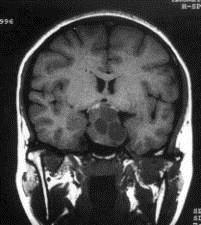

问题 病历摘要:??患者男性,35岁。性功能减退2年,视力下降6月。既往体健。体检:神清,皮肤细腻,毛发稀疏。视力左眼0.3,右眼0.5,双瞳等大等圆,直径3.5mm,对光反射稍迟钝,双颞侧偏盲,双眼底视神经乳头原发性萎缩,余神经系统未见异常。 患者出现上述情况,作何处理?提示:术后第?1日患者尿量300ml/小时,尿比重1.002